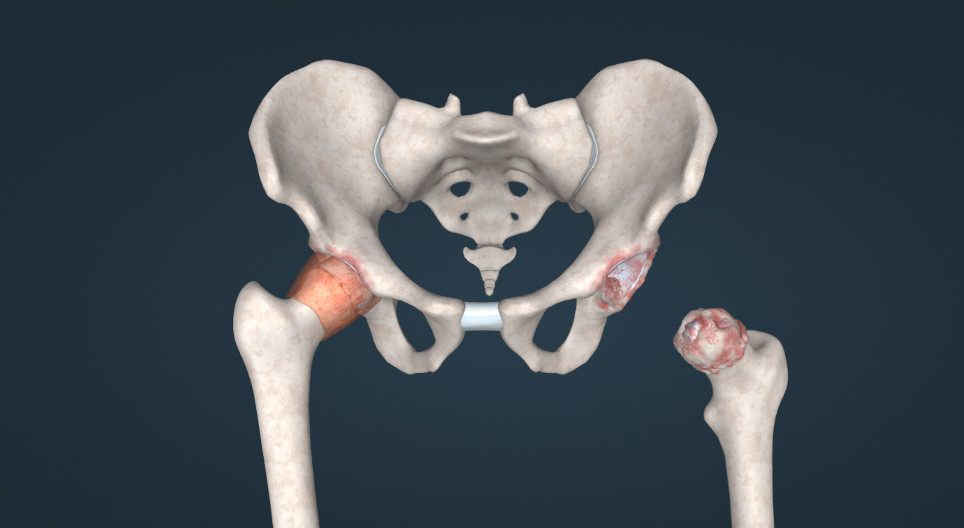

Osteoarthritis encompasses a range of joint diseases, with osteoarthritis being the most common degenerative type. It primarily involves the gradual breakdown of hyaline cartilage, which leads to subsequent changes in the subchondral bone and potential damage to periarticular structures, leading to decreased muscle function around the joint.